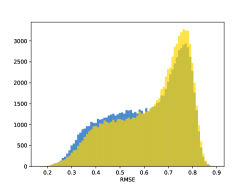

To visualise similarity metrics that compare image pairs (RMSE, SRE, SSIM) two metric distributions are generated: intra-similarity and inter-similarity. For each compared sample 300 random images are selected. The inter-similarity distribution is calculated for each image pair combination from both compared samples e.g. generated images of COVID-19 and real images of COVID-19. For the intra-similarity, all pairs of images in a single sample e.g real images of COVID-19 are considered. By comparing the shape of intra-similarity for the training subsample (Dataset) with the inter-similarity of training and generated samples the quality of the generated sample can be judged. It is also possible to compare in this way between the four image classes present in the dataset. The resulting distributions of inter-similarity of COVID-19 and the three remaining classes are compared in Fig. 4 to distributions of intra-similarity of the COVID-19 sample for each metric. All metrics, as expected based on available medical evidence Rubin et al. (2020), indicate that there are visible differences not only between COVID-19 and normal samples but also between viral pneumonia and lung opacity. Therefore, all classes should be distinguishable.

To visualise differences between synthetic and real samples distributions are generated for each of the RMSE, SRE and SSIM metrics: intra-similarity and inter-similarity. For each compared sample 300 random images are selected. The inter-similarity distribution is calculated for each image pair combination from both compared samples e.g. generated images of COVID-19 and real images of COVID-19. For the intra-similarity, all pairs of images in a single sample e.g real images of COVID-19 are considered. The distributions for generated samples describe very well the distributions for corresponding real images as shown in Fig. 6.

The quality of generated images is also confirmed with classical similarity metrics. The distributions of those similarity measures between generated and real images are compared for each sample with the distribution obtained within the real samples 6. The distributions for generated samples describe very well the distributions for corresponding real images. For an example see the results for the SSIM metric presented in Fig. 10. The small visible differences are almost insignificant compared to differences observed between the classes in Fig. 4.